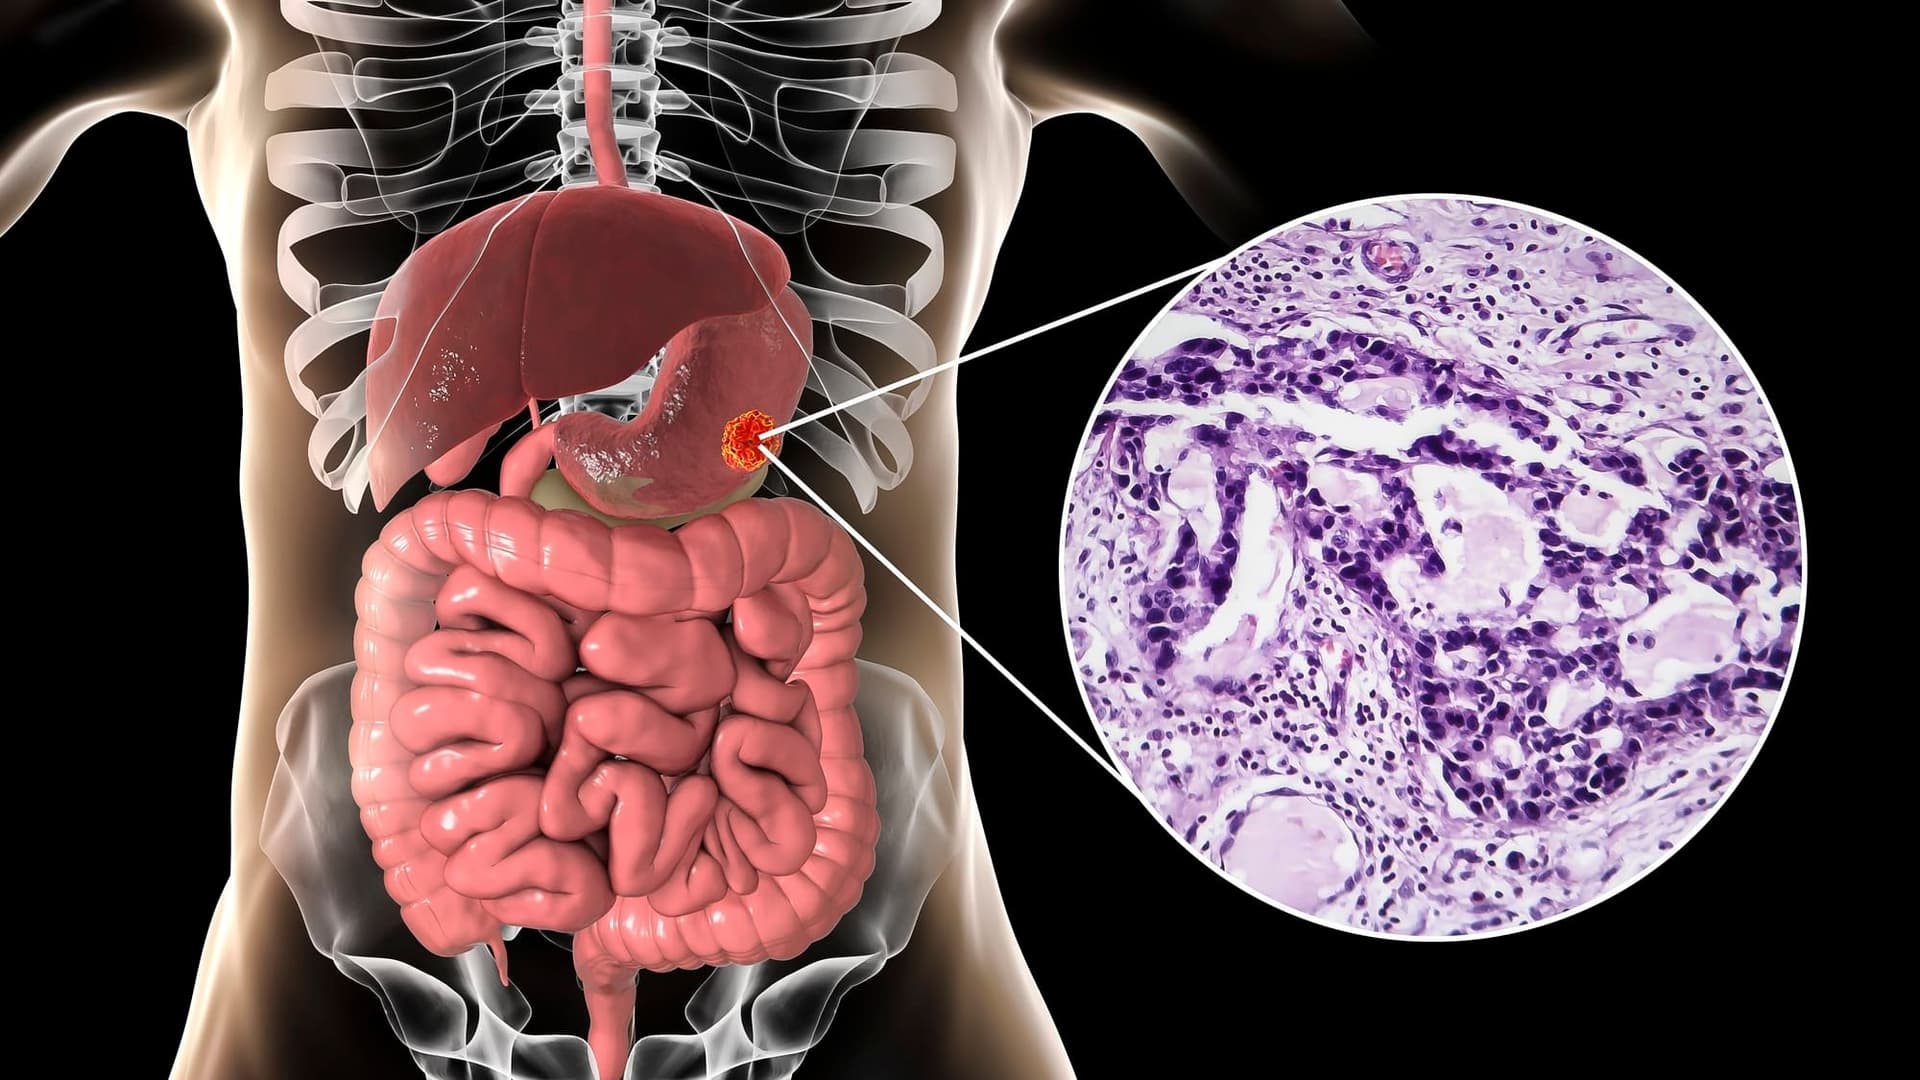

Аденокарцинома шлунка: діагностика, лікування та рекомендації

Рак шлунка є третьою в світі провідною причиною смертей, пов’язаних із онкологією, що становить приблизно 1 з 12 усіх смертей від онкологічних захворювань. За оцінками, у 2018 році було зареєстровано 783 000 смертей від раку шлунка, що трохи відстає від кількості смертей від раку легенів і печінки. Рак шлунка є п’ятим за поширеністю раком у світі з понад мільйоном нових випадків щорічно. Східна Азія має найвищий рівень захворюваності на рак шлунка. Загалом захворюваність і кількість смертей, пов’язаних із раком шлунка, зросла за останні 2-3 десятиліття.

Езофагогастродуоденоскопія (ЕГД) з біопсією є золотим стандартом діагностики раку. Ендоскопіст повинен ретельно зафіксувати розташування пухлини в шлунку, оскільки це має критичні наслідки для лікування. Згідно з класифікацією TNM Американського об’єднаного комітету з питань раку (AJCC) і Союзу з міжнародної боротьби з раком (UICC) восьмого видання, пухлини стравохідно-шлункового з‘єднання з епіцентром менше 2 сантиметрів (см) у проксимальному відділі шлунка класифікуються як стравохідні ракові захворювання; ті, що перевищують 2 см з розповсюдженням у шлунок, визначаються як рак шлунка. Потрібно взяти кілька (6-8) біопсій. Для уражень розміром менше 2 см досвідчений спеціаліст може розглянути ендоскопічну резекцію слизової оболонки (EMR) або ендоскопічну резекцію підслизової оболонки (ESD), що може бути як діагностичним, так і терапевтичним методом залежно від результатів біопсії зразка. Звіт про патологію біопсії повинен включати наявність інвазії, гістологічний підтип (кишковий або дифузний) і ступінь диференціації пухлини.